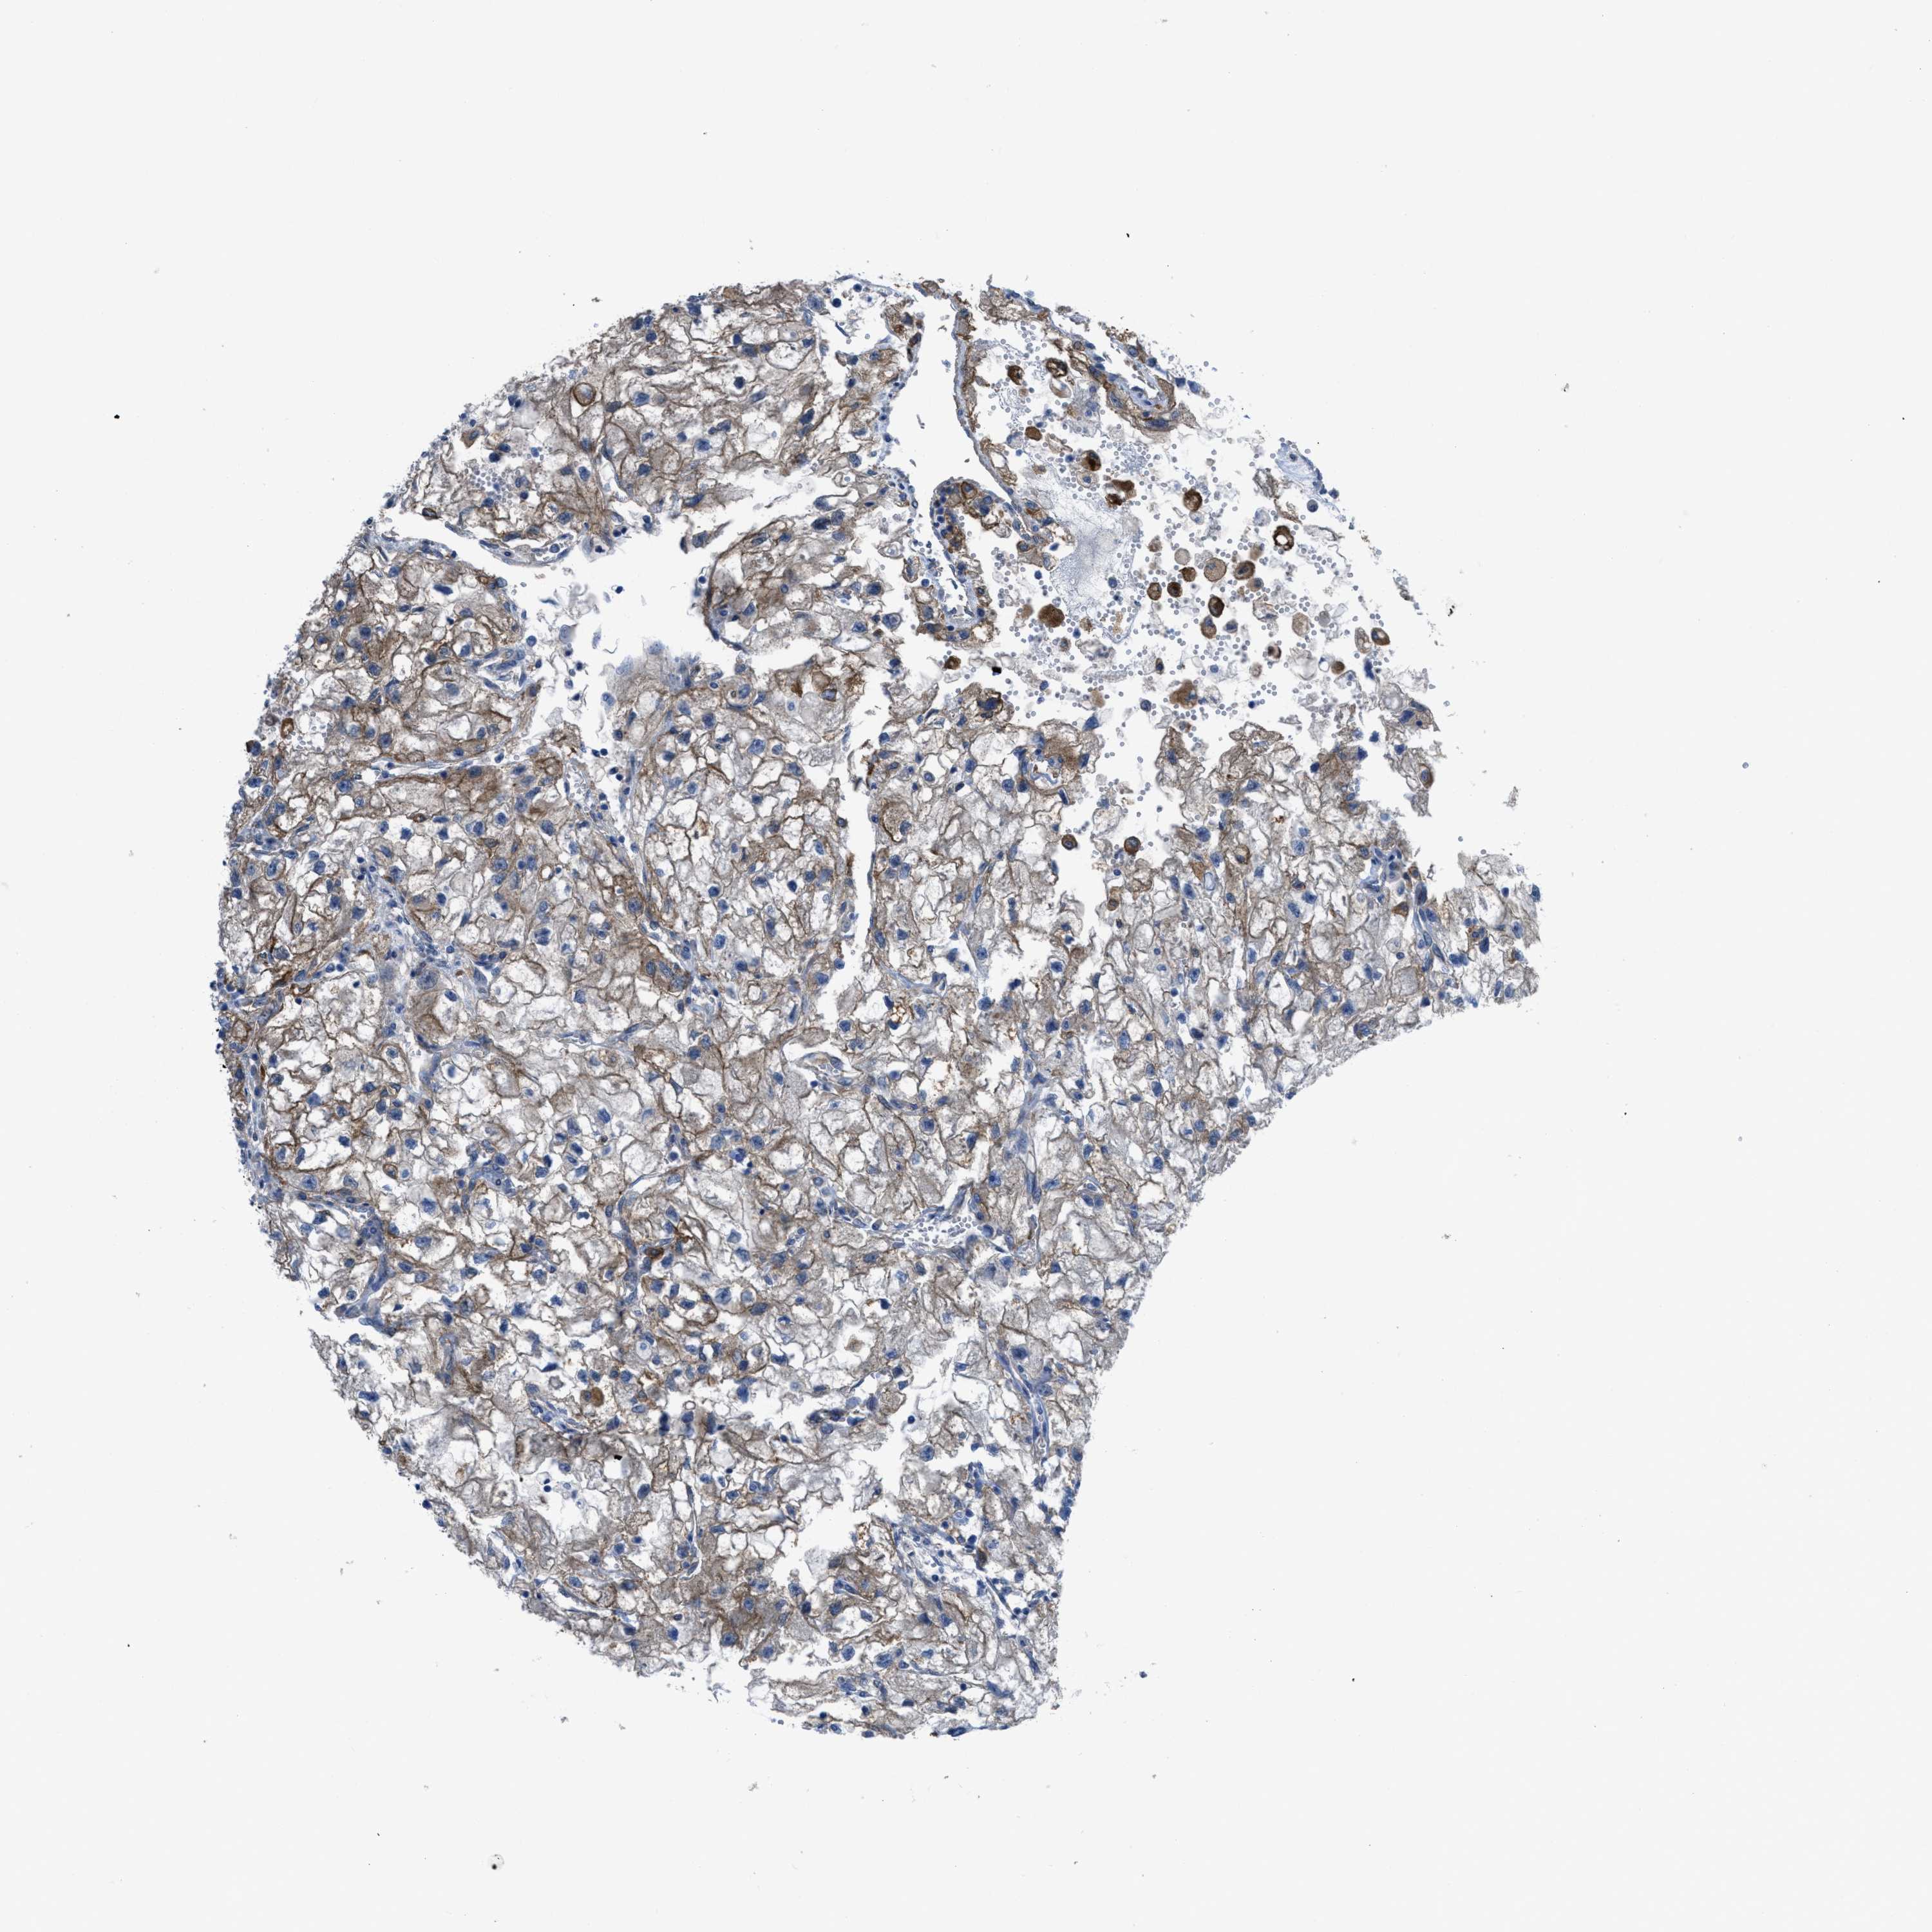

KIDNEY RENAL CLEAR CELL CARCINOMA (VALIDATION) - Interactive survival scatter ploti

The Survival Scatter plot shows the clinical status (i.e. dead or alive) for all individuals in the patient cohort, based on the same data that underlies the corresponding Kaplan-Meier plots. Patients that are alive at last time for follow-up are shown in blue and patients who have died during the study are shown in red.

The x-axis shows the expression levels (FPKM) of the investigated gene in the tumor tissue at the time of diagnosis. The y-axis shows the follow-up time after diagnosis (years). Both axes are complimented with kernel density curves demonstrating the data density over the axes. The top density plot shows the expression levels (FPKM) distribution among dead (red) and alive patients (blue). The right density plot shows the data density of the survived years of dead patients with high and low expression levels respectively, stratified using the cutoff indicated by the vertical dashed line through the Survival Scatter plot. This cutoff is automatically defined based on the FPKM cutoff that minimizes the p-score. The cutoff can be changed by dragging the vertical line or by entering a cutoff value in the square labeled "Current cut-off".

Under the Survival Scatter plot the p-score landscape (black curve; left axis) is shown together with dead median separation (red curve; right axis). Dead median separation is the difference in median mRNA expression between patients who have died with high and low expression, respectively. It is calculated as follows: median FPKM expression of dead patients with high expression - median FPKM expression of dead patients with low expression. This is intended to aid the user in visually exploring custom cutoffs and the associated p-scores and dead median separation.

Individual patient data is displayed and can be filtered by clicking on one or more of the category buttons on the top of the page. Categories describing expression level and patient information include: high, low, alive, dead, female, male and tumor stages. The scale of the x-axis can be toggled between linear and log-scale by clicking on the "x log" button. Mouse-over function shows TCGA ID, patient information and mRNA expression (FPKM) for each patient.

& Survival analysisi

Kaplan-Meier plots summarize results from analysis of correlation between mRNA expression level and patient survival. Patients were divided based on level of expression into one of the two groups "low" (under cut off) or "high" (over cut off). X-axis shows time for survival (years) and y-axis shows the probability of survival, where 1.0 corresponds to 100 percent.

EGFR is not prognostic in Kidney Renal Clear Cell Carcinoma (validation)

Best expression cut offi

Based on the FPKM value of each gene, patients were classified into two groups and association between prognosis (survival) and gene expression (FPKM) was examined. The best expression cut-off refers the FPKM value that yields maximal difference with regard to survival between the two groups at the lowest log-rank P-value. Best expression cut-off was selected based on survival analysis .

When clicking on this number, the vertical dashed line indicating cut-off, the interactive survival plot, and the Kaplan-Meier curve will be adjusted to show results based on the best expression cut-off.

: 44.55

TCGA RNA samplesi

RNA-seq data is reported as average FPKM (number Fragments Per Kilobase of exon per Million reads), generated by the The Cancer Genome Atlas (TCGA) .

Normal distribution across the dataset is visualized with box plots, shown as median and 25th and 75th percentiles. Points are displayed as outliers if they are above or below 1.5 times the interquartile range. FPKM values of the individual samples are presented next to the box plot.

Average pTPM 89.3

Number of samples 100